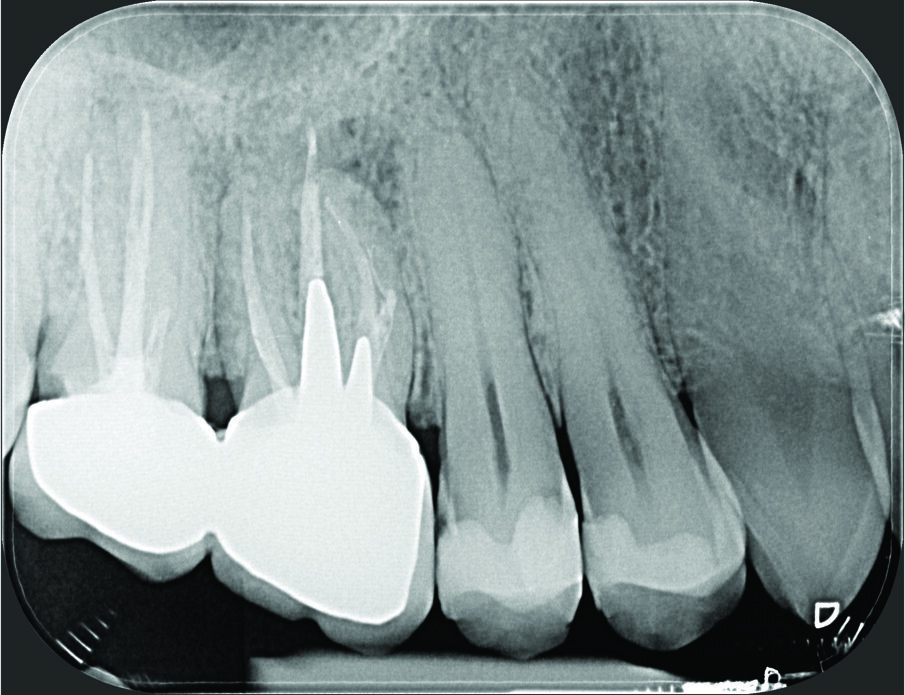

Fig. 1a - Il paziente è stato inviato per la terapia chirurgica della radice mesiovestibolare del primo molare superiore di destra.

Fig. 1b - Una radiografia presa con diversa angolazione sembra confermare che l’unica radice coinvolta nella lesione periapicale è la mesiovestibolare.